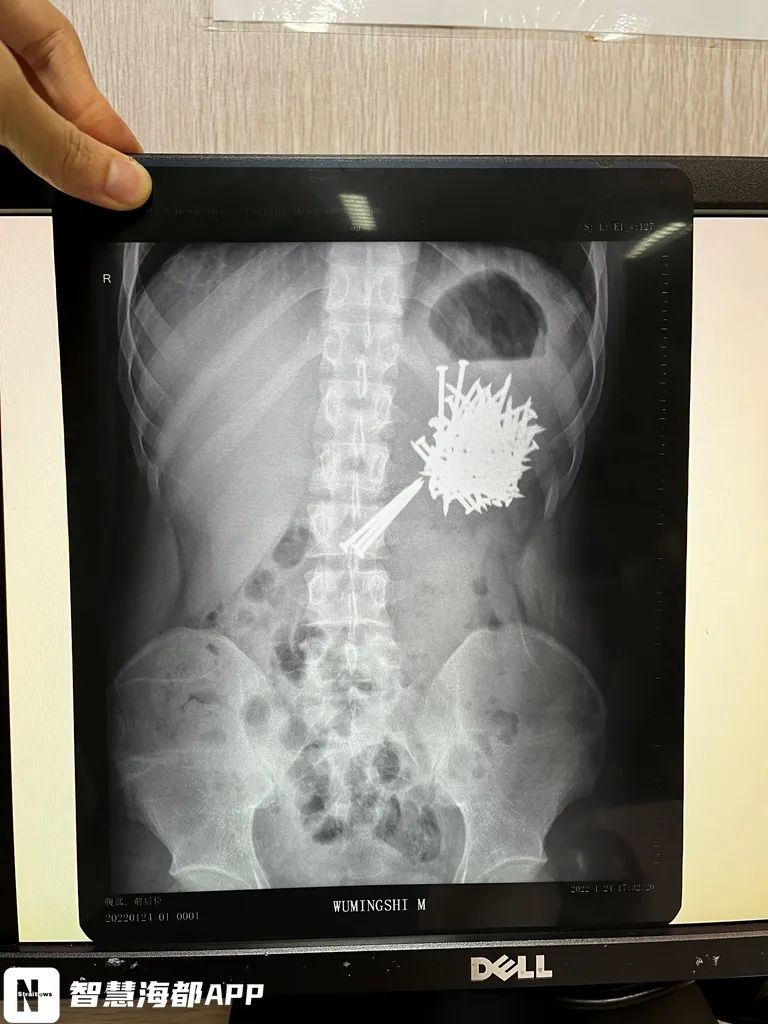

1月28日晚,21岁小伙丁丁(化名)吞下36根尖锐的铁钉,腹痛5小时后被民警紧急送往福建省第二人民医院救治。

医生检查发现,丁丁胃内滞留大量钉子状物体,头端异常尖锐。“铁钉一旦滑入小肠,导致肠穿孔,进而就可危及生命,后果不堪设想!”医生说。

让人意想不到的是

就在1月25日

丁丁还“吃了”

61根如此大小的铁钉

被紧急送往福州市第一医院